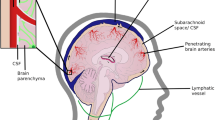

Alzheimer’s disease (AD) is characterized by amyloid-beta (Aβ) deposits and hyperphosphorylated tau tangles within the brain. To maintain brain homeostasis, various clearance systems exist to eliminate extracellular Aβ from the central nervous system, including the glymphatic pathway [13]. AQP4, which is located perivascular on astrocyte endfeet, plays a vital role in proper functioning of the glymphatic system (Fig. 1) [14].

Amyloid-beta clearance via the glymphatic system. Aquaporin-4 (AQP4) water channels facilitate the continuous interchange between cerebrospinal fluid and brain interstitial fluid by convective flow movement. These water channels are positioned on the endfeet of astrocytes situated at the outer layer of the artery and vein. The glymphatic flow guides proteins, such as amyloid-beta, and metabolites to the perivenous space via AQP4 water channels, thus promoting their efficient elimination from the central nervous system outside the brain